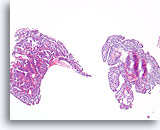

Papillair neoplasma, Borst FNA, Celblok.

Een kleine vergroting van de residuele naaldspoeling van de patiënt in afbeelding 39-42 toont een duidelijk papillaire architectuur. Let op de gelijksoortigheid van de ductale populatie in dit hele veld. Dit monotone patroon duidt meer op een papillair carcinoom dan een papilloom.

40X

Papillair neoplasma, Borst FNA, Celblok.

Een kleine vergroting van de residuele naaldspoeling van de patiënt in afbeelding 39-42 toont een duidelijk papillaire architectuur. Let op de gelijksoortigheid van de ductale populatie in dit hele veld. Dit monotone patroon duidt meer op een papillair carcinoom dan een papilloom.

40X

Papillair carcinoom, Borst FNA, Celblok.

Sterkere vergroting van de patiënt uit afbeelding 39-43 toont een fibrovasculaire kern (open pijl) en een cribriform gebied dat consistent is met een papillair carcinoom (pijl).

10X

Papillair carcinoom, Borst FNA, Celblok.

Sterkere vergroting van de patiënt uit afbeelding 39-43 toont een fibrovasculaire kern (open pijl) en een cribriform gebied dat consistent is met een papillair carcinoom (pijl).

10X

Papillair carcinoom, Borst FNA, Celblok.

Een ander cribriform gebied (pijl) en een fibrovasculaire kern (open pijl) kunnen gemakkelijk worden onderscheiden.

10X

Papillair carcinoom, Borst FNA, Celblok.

Een ander cribriform gebied (pijl) en een fibrovasculaire kern (open pijl) kunnen gemakkelijk worden onderscheiden.

10X

Papillair carcinoom, Borst FNA, Celblok.

Een sterkere vergroting van het diagnostische cribriforme patroon in afbeelding 45 toont een monotone celpopulatie met gerandomiseerde polariteit die gladde, ronde ruimten vormt. Necrotisch materiaal is focaal aanwezig in één lumen.

40X

Papillair carcinoom, Borst FNA, Celblok.

Een sterkere vergroting van het diagnostische cribriforme patroon in afbeelding 45 toont een monotone celpopulatie met gerandomiseerde polariteit die gladde, ronde ruimten vormt. Necrotisch materiaal is focaal aanwezig in één lumen.

40X